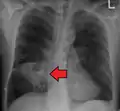

Pulmonary abscess on CXR

Lung abscesses are often on one side and single involving posterior segments of the upper lobes and the apical segments of the lower lobes as these areas are gravity dependent when lying down. Presence of air-fluid levels implies rupture into the bronchial tree or rarely growth of gas forming organism.